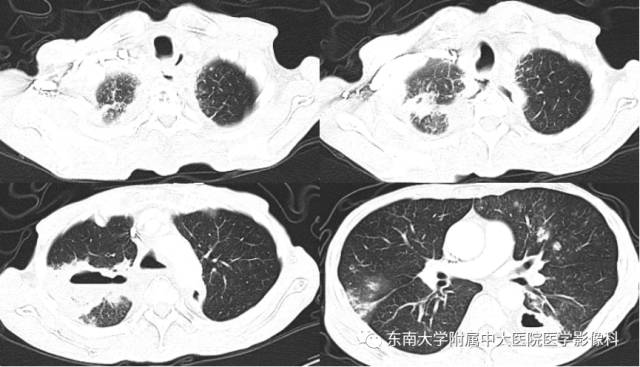

男,60岁,因“食管癌术后5年余,进食呛咳10天”入院。

影像学表现